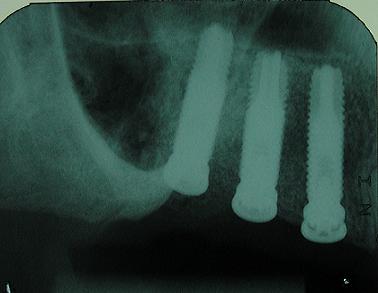

RADIOGRAFIAS PERIAPICAIS DOS IMPLANTES COM PRÓTESES